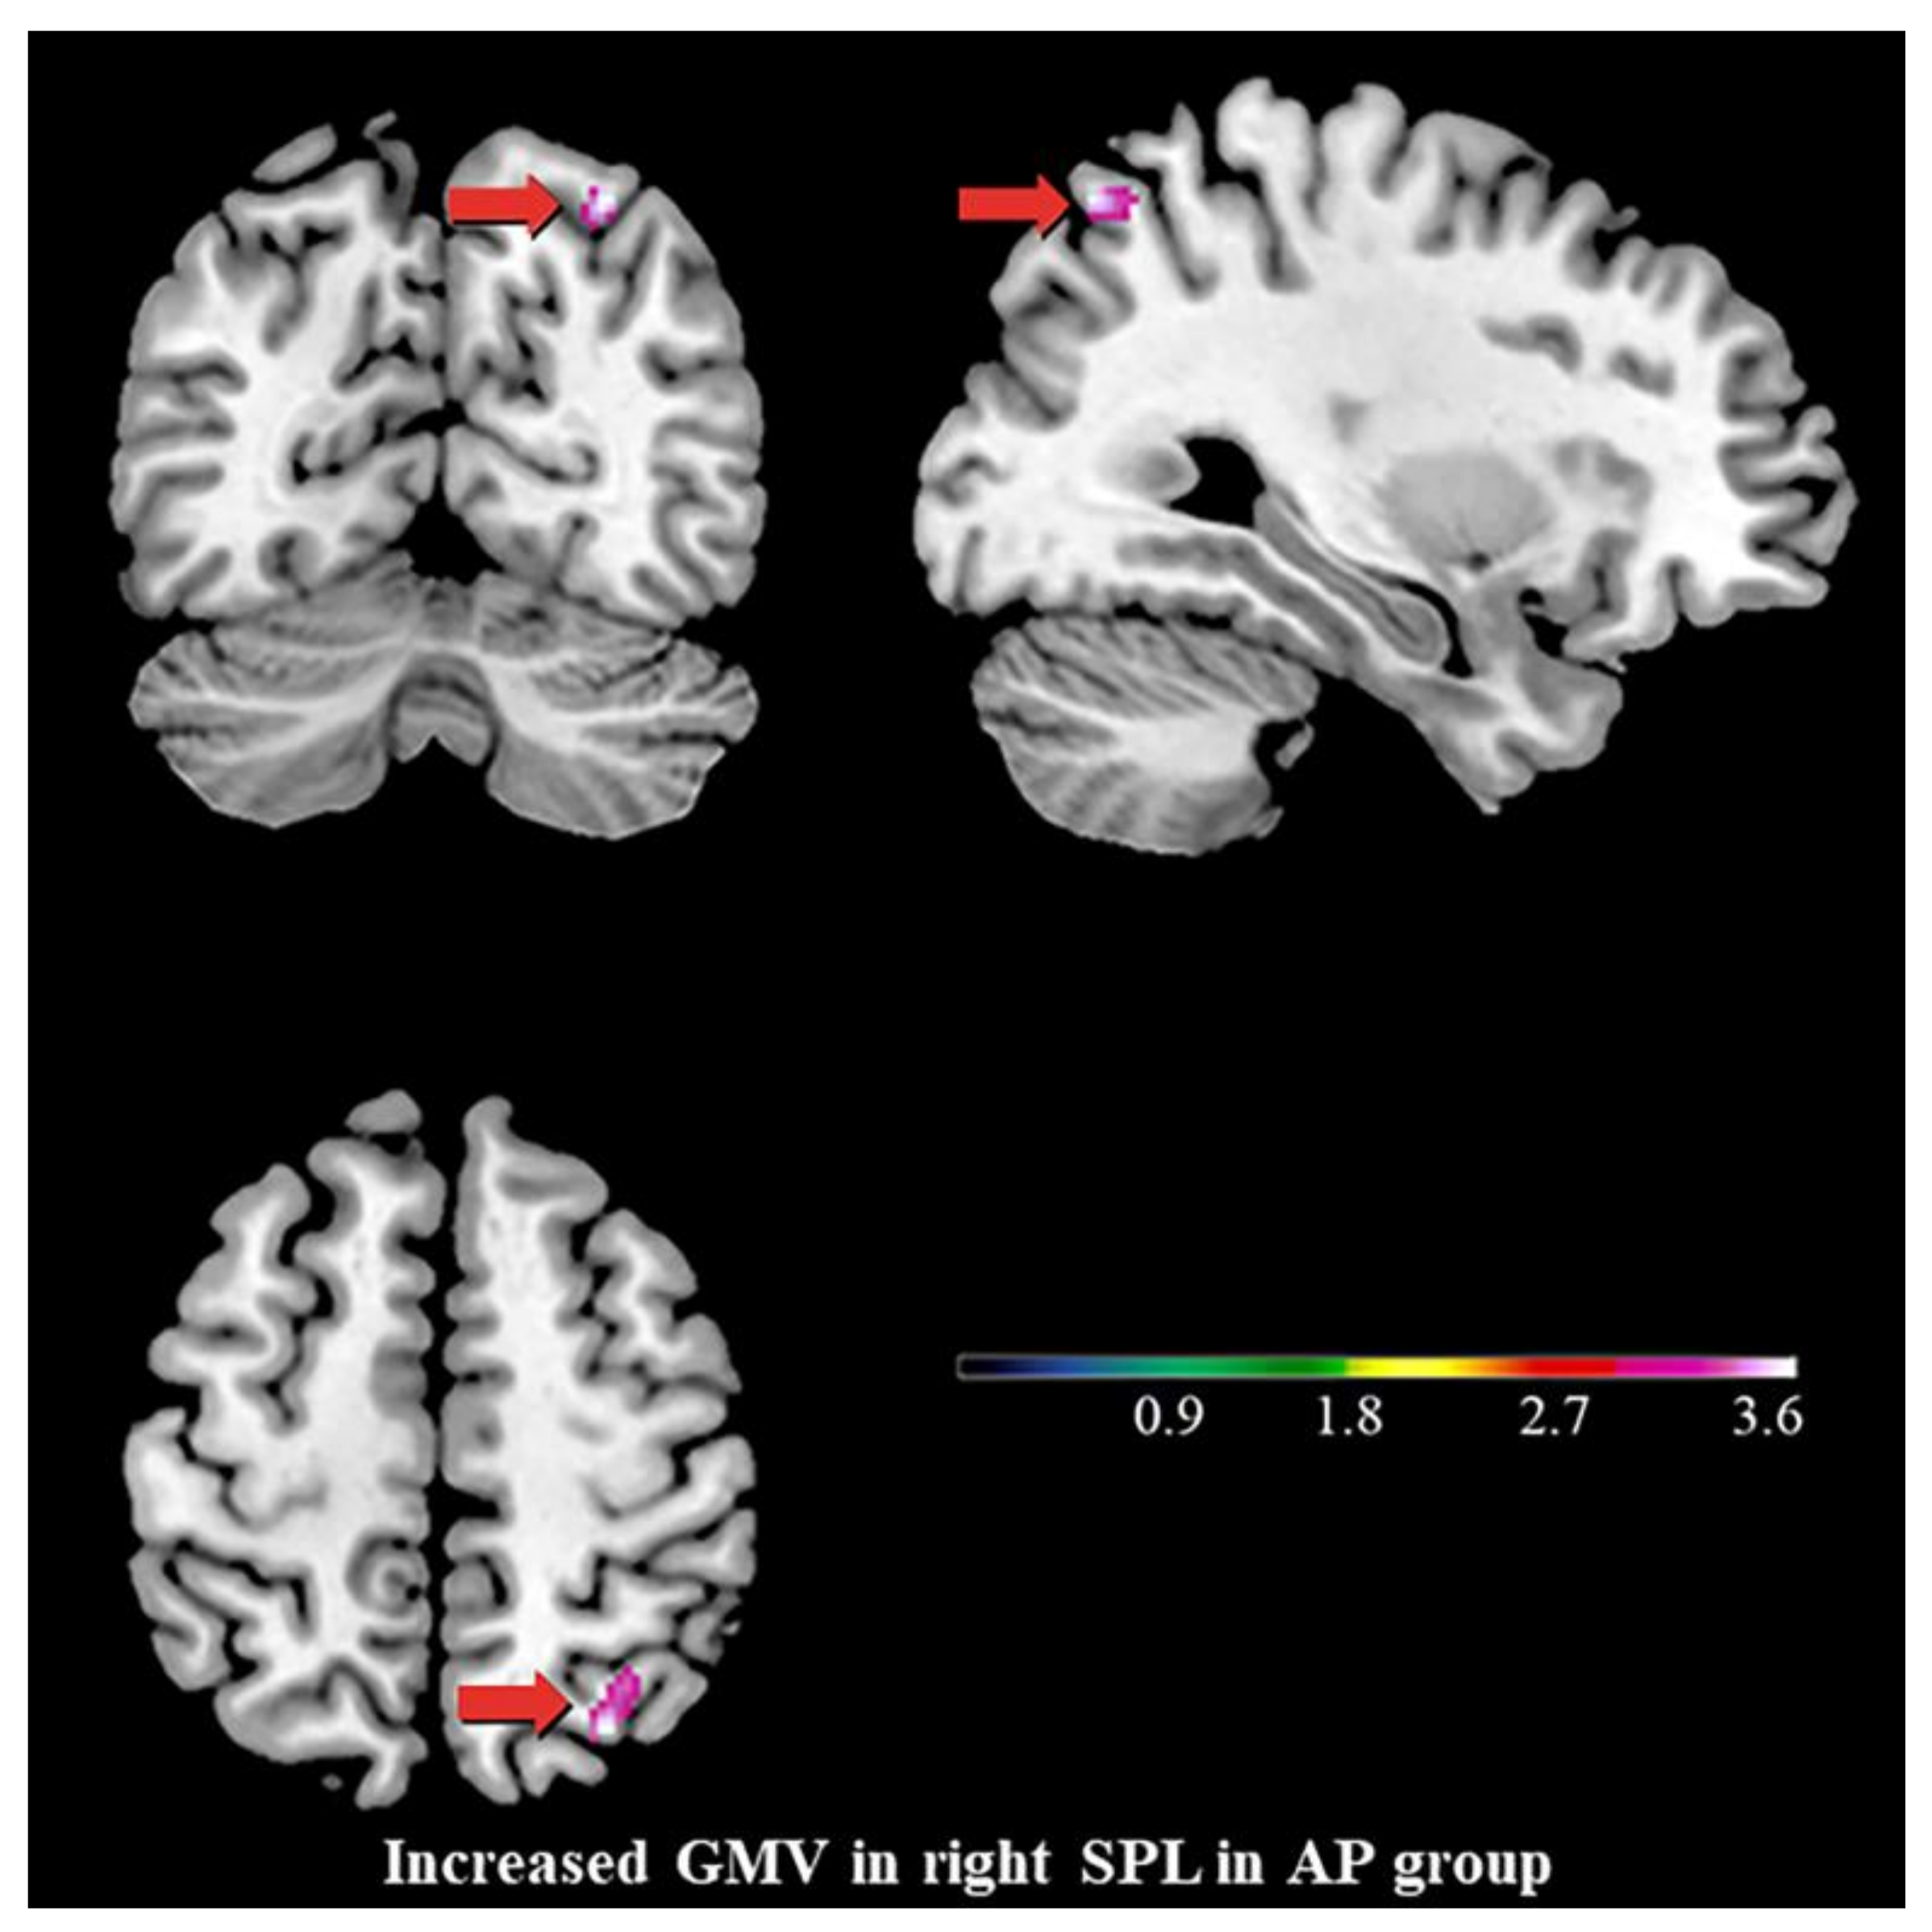

3.2. Differences in GMV

4.2. Increased GMV of the Right SPL, the Stigmata of Childhood AP?